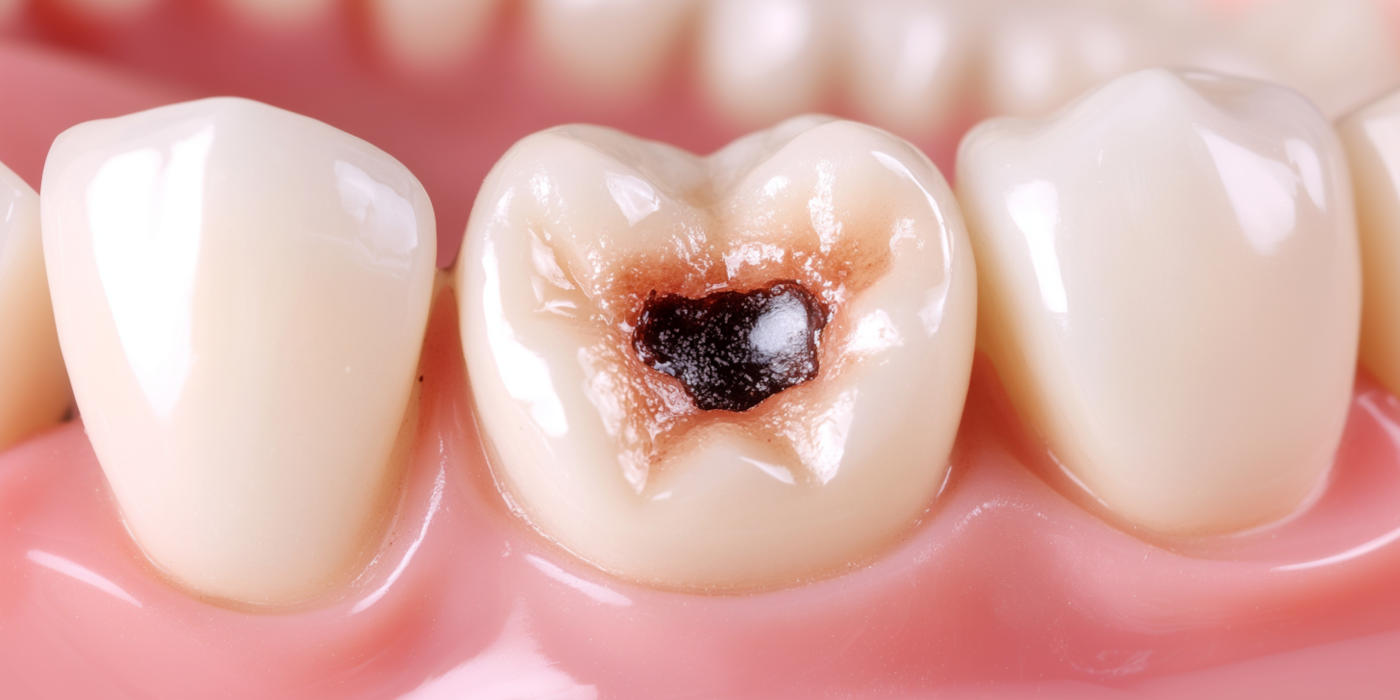

🦷 Soins conservateurs – carie de petite taille

Lorsqu’une carie est détectée à un stade précoce, un soin conservateur permet de la traiter efficacement.

La partie atteinte est retirée, puis remplacée par un matériau esthétique et résistant.

👉 L’objectif : préserver votre dent naturelle, éviter l’évolution de la carie et retrouver confort et esthétique.

🦷 Soins conservateurs – carie de grande taille

Inlay, onlay ou couronne

Si la dent est plus fragilisée, des restaurations sur mesure sont proposées :

- Inlay ou onlay pour renforcer la dent tout en conservant un maximum de structure saine.

- Couronne dentaire pour protéger durablement une dent très atteinte.

👉 Ces solutions permettent de restaurer la solidité, la fonction masticatoire et l’esthétique de la dent.